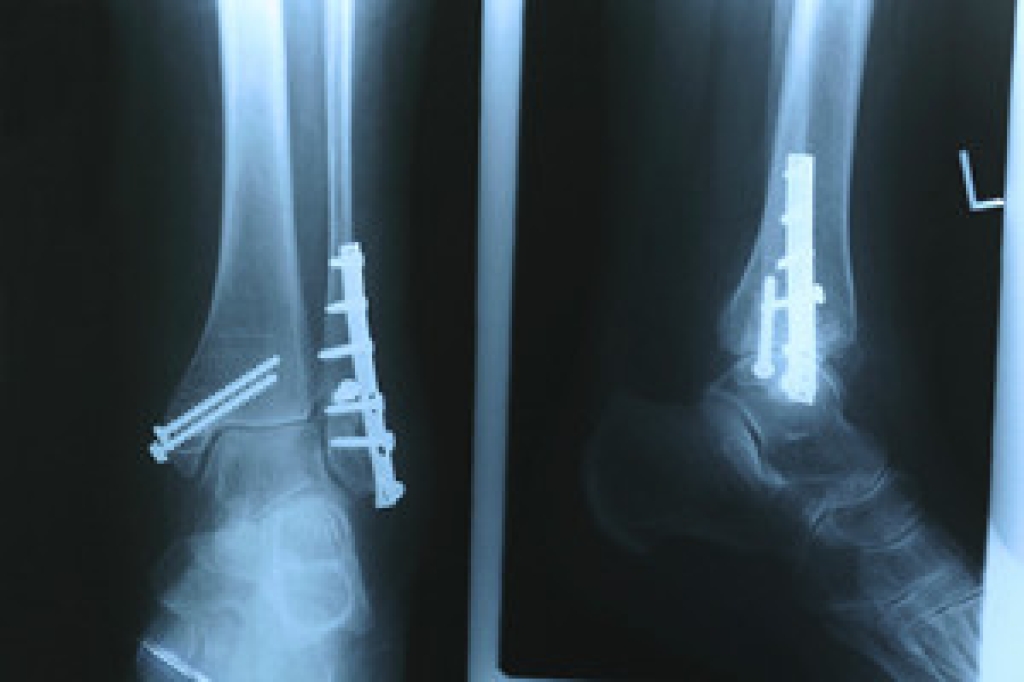

Treatments for plantar fasciitis include resting and icing the affected foot, stretching the foot, taking medications to reduce inflammation, and wearing orthotics. In severe cases where pain does not improve with conservative treatments, injections or surgery may be recommended.